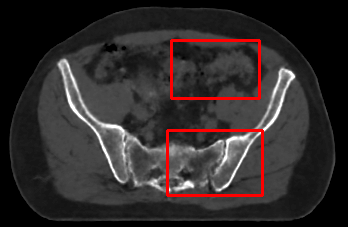

In the MRI CT translation in the Gold Atlas dataset (Fig. 8), major bones and muscles are translated faithfully. Yet, diffusion sampling leads to some inaccuracies in the outline of bones and hallucinations of the textures of inner organs. Conversely, regression sampling faithfully translates bones while still blurring the inner organs and generating artifacts. This indicates that rendering CTs is under-defined by the given MRI guidance alone.

In the quantitative analysis (Tab. 3), we found a slightly increased performance of sampling with over regression sampling in terms of PSNR and accuracy of the downstream task. As performance gains are marginal and the assessment is based on few () test cases, we still assume the performance of diffusion and regression to be similar.

Diffusion sampling YODA results in hallucinated organ shapes and textures that smoothen out and disappear when increasing the in Exp sampling or when using regression sampling. Regression sampling creates some artifacts. Note that, for all methods, the translation quality for inner organs is rather poor, whereas bone and muscle translation is reliable.

When benchmarking on the more heterogeneous and lower-quality BraTS dataset (Tab. 2, left), regression sampling of YODA achieved significantly better images than all competing methods in terms of PSNR, SSIM, and downstream glioma segmentation. Similar results were obtained in the IXI dataset (Tab. 2, right), where YODA significantly outperformed all competing methods in SSIM and PSNR. In the full-brain segmentation conducted from the synthetic images, YODA’s images were significantly better than all competing methods in at least either the Dice score or the HD. In the MRI CT task on the small pelvic dataset, regression and ExpA sampling achieved the highest SSIM, whereas the DB of Choo et al. [31] had the highest PSNR. Both, regression and ExpA sampling YODA also performed competitively in the downstream segmentation task. Note that, for all methods, the translation of inner organs was rather poor and included either texture hallucination (ResViT, I2I-Mamba, diffusion-sampling YODA) or an over-smooth image appearance (Choo et al. [31], SelfRDB, SynDiff, ExpA and regression sampling YODA, Fig. 8).